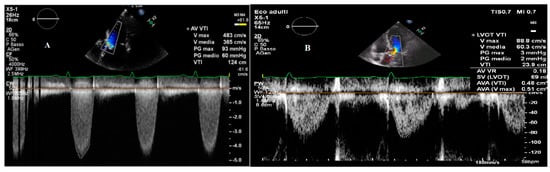

2.1. Transvalvular Pressure Gradients

2.2. Aortic Valve Area